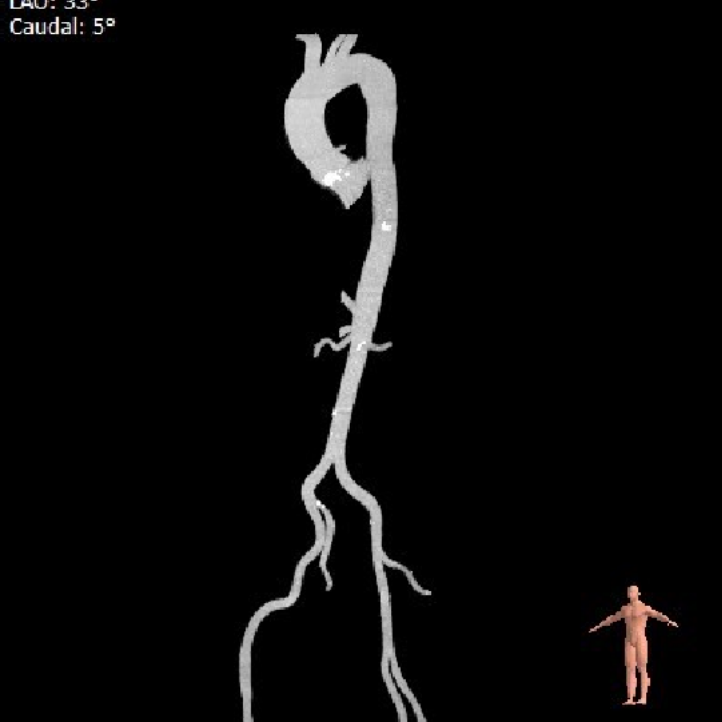

外周血管及主动脉弓解剖

双侧血管内径良好,所见主动脉血管壁见少量钙化形成。

患者双侧血管内径良好,术中选择右股动脉为主入路,左侧位辅入路。